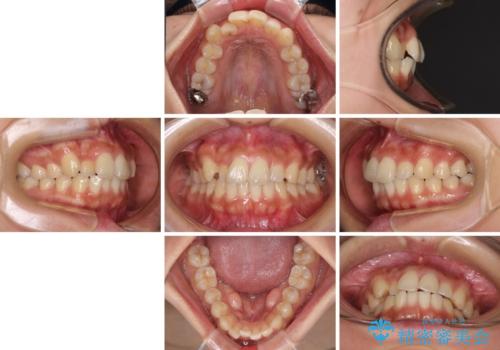

【モニター】歯列が狭くデコボコが気になる 急速拡大装置を用いたインビザライン矯正

- 奥歯の咬み合わせと治療を放置したまま奥歯を気にして来院された患者様です。

上顎骨の幅が下顎骨よりも小さいので、拡大装置により骨幅を広げて上下関係を改善し、その後インビザラインにて歯並びを整えることとしました。

矯正治療後には土台のままとなっている歯をセラミッククラウンにて補綴治療を行うこととしました。

上下の骨幅を改善したことで、スムーズに歯列矯正を行うことができました。

土台のまま放置されていた歯は土台の状態で咬み合っていましたが、急速拡大を行った際に咬み合わせが著しく挙上されたため、その際に土台を大きくすることで咬み合う歯との距離を確保しました。